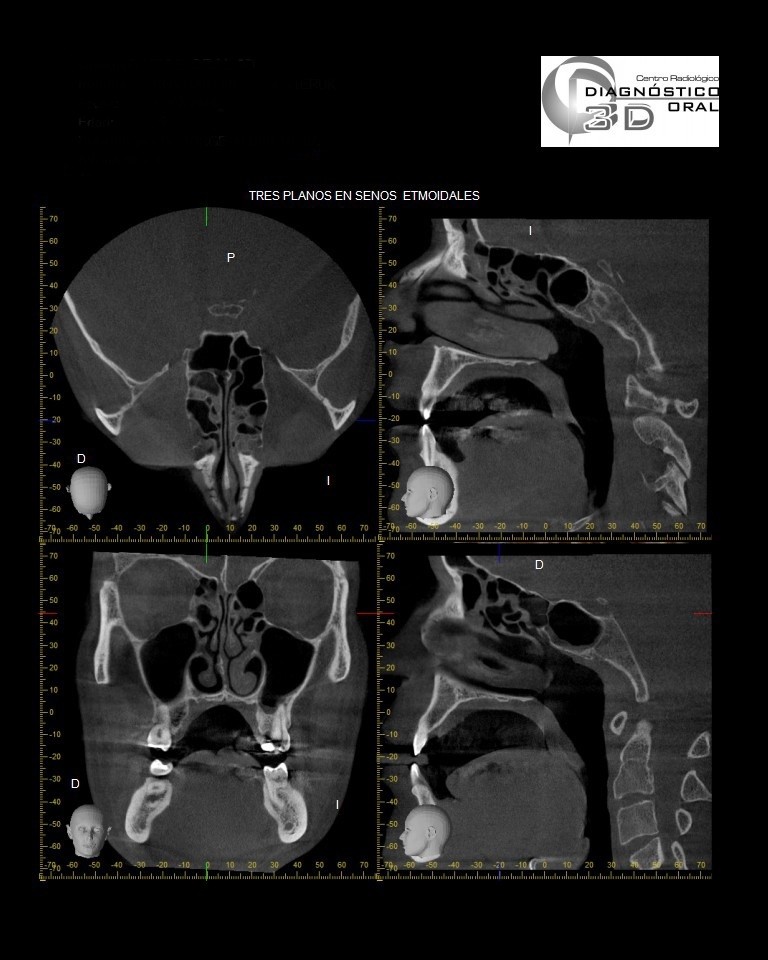

El Centro Radiológico Diagnóstico Oral 3D, es una empresa antioqueña que ofrece a sus pacientes desde el año 2009, tecnología de vanguardia en radiografías tridimensionales con calidad fotográfica. Las posibilidades para mejorar la eficacia en los diagnósticos bucales son evidentes, también lo son las posibilidades de manipulación de imagen. El sistema de imágenes en 3D ofrece detalles sin precedentes, convirtiéndola en la opción idónea para la mayoría de aplicaciones odontológicas, incluyendo implantes, tratamiento de conductos, ortodoncia, odontopediatría, periodoncia y cirugía

El mayor beneficiado con el uso de esta tecnología es el paciente, el cual podrá ser evaluado en todas sus dimensiones con una baja dosis de radiación, con un costo accesible y sin contaminar  el medio ambiente. Dependiendo de la necesidad del paciente, hay varios tipos de tomografías y los especialistas en el área odontológica hacen uso de ellas según su especialidad.

Evaluación de patologías dentales y maxilofaciales

Evaluación pre y postoperatoria de cirugías maxilofaciales